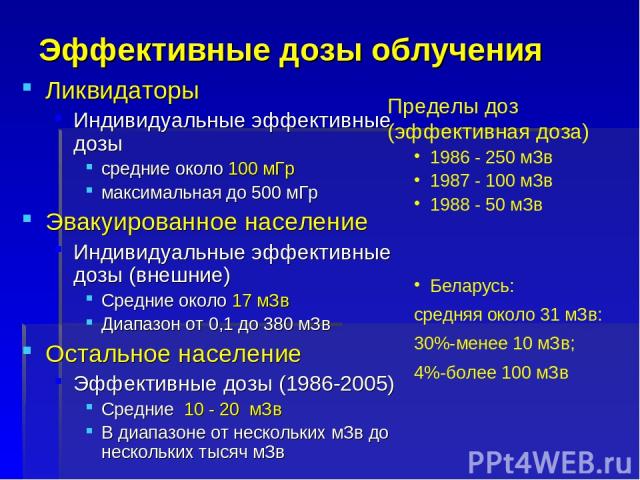

Изучение дозы излучения при рентгеновских исследованиях: визуализация